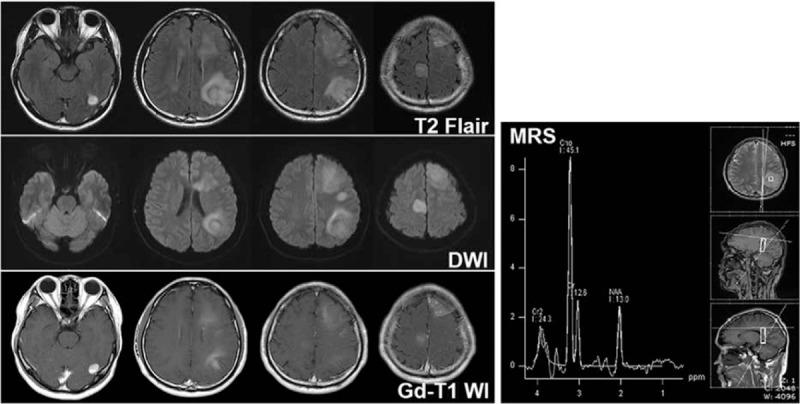

Multiple cerebral gliomas (MCGs), usually classified into multifocal and multicentric subtypes, represent major diagnostic challenges as their clinical, radiologic, and pathohistological features are not uniform, often mimicking brain metastatic tumors or central nervous system inflammatory demyelinating diseases (IDD).

Here, we report a rare case of MCGs with isolated seizures and 4 lesions in the brain, that was initially misdiagnosed as IDD during treatment.

The pathological diagnosis was astrocytoma, which was classified as a World Health Organization grade II glioma.

Diagnostic imaging is valuable in differential diagnosis. Magnetic resonance spectroscopy is a promising technique for the assessment and characterization of lesions, though its role in definitive diagnosis is not yet defined. Brain tissue biopsy remains the golden standard for definitive diagnosis. In China, for various reasons, craniotomy biopsy is not performed routinely in patients with multiple intracranial lesions, and stereotactic cranial biopsy may be a more viable option because of its safety and cost-effectiveness. In summary, this case demonstrates that MCGs need to be included in the differential diagnosis of unknown intracranial multiple lesions.